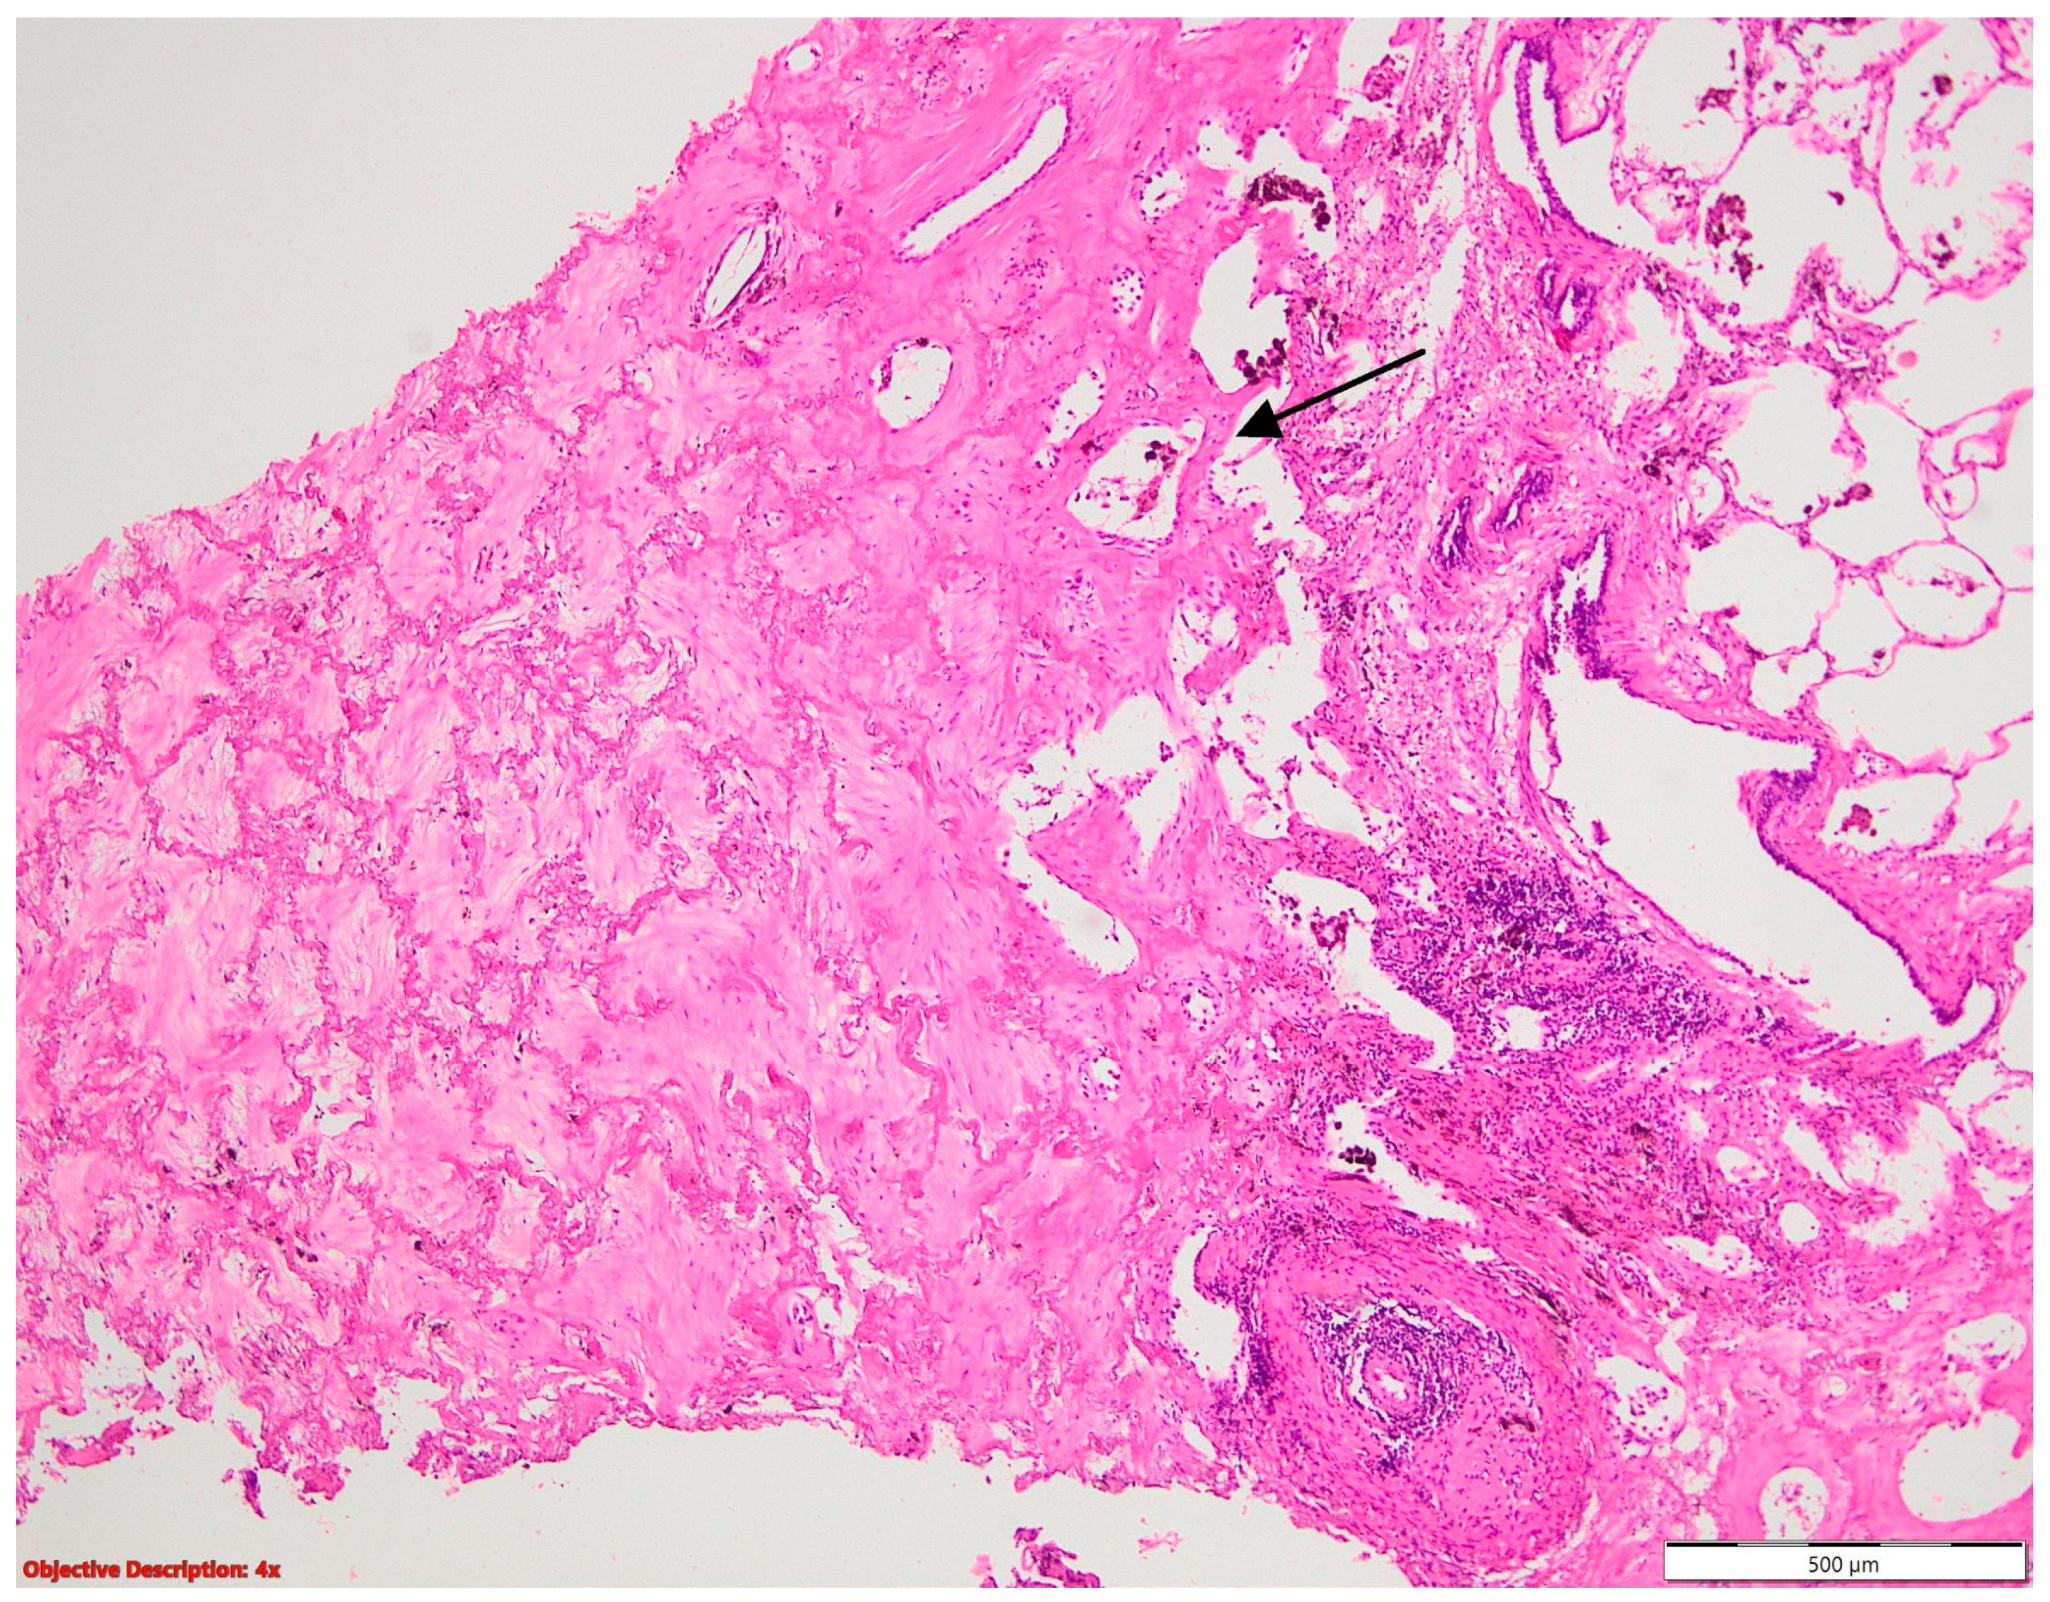

A histopathological examination of surgical resection specimens highlighted the presence of the following associations between NSCLC and other tumoral and nontumoral, and infectious and noninfectious pathological lesions, including nine cases of granulomatous inflammation, ten cases of fibronodular lesions, five cases of fibronecrotic nodules (Figure 1), two nodular calcifications, four instances of osseous/osteomedullary metaplasia, three cases of pneumoconiosis, two benign tumors, four lung infarctions, one instance of aspiration pneumonia, and one meningothelial-like nodule (Table 1).

Figure 1. Fibronecrotic nodule (left side) in the lung parenchyma (right side); HE, 40×.